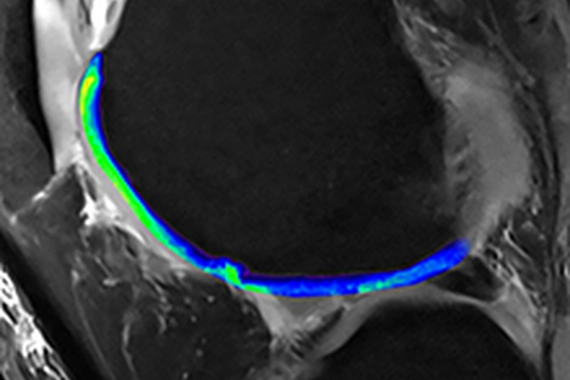

Skeletal Mitochondria

Diseases of aging and regenerative medicine (DARe)

The DARe group is focused on elucidating and targeting the molecular mechanisms underlying diseases of aging and developing potential regenerative pharmacological interventions that restore tissue integrity and function.